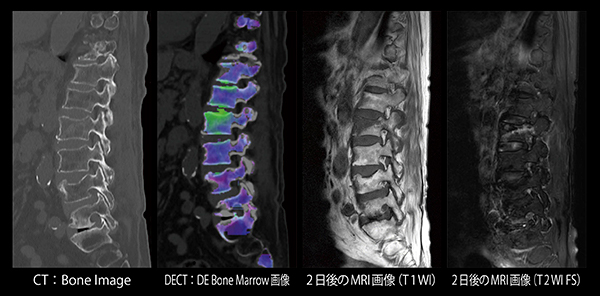

腰椎圧迫骨折評価におけるBone Marrow解析の有用性

稲田発輝(天草地域医療センター放射線部)

【背 景】74歳,女性。交通外傷にて来院。頭頸部および腰部に疼痛の訴えがあった。全身の精査目的にてDual Energy CT(DECT)検査を施行した。

【所 見】Th12,L1,L2,L4に圧迫骨折後の変化,L5/S1では終板変性が認められた。L2圧迫骨折部では,DE Bone Marrowにて骨髄浮腫が認められたが,他の骨折部については,浮腫を示唆する異常は認められなかった。2日後に腰椎MRI検査が施行され,DE Bone Marrowにて浮腫が認められた部位に一致したT1WI低信号,T2WI FS高信号が認められた。

【訴求ポイント】椎体圧迫骨折診断において,新規骨折および陳旧性骨折が混在している場合には,形態評価のみでは診断・鑑別に苦慮する。MRIによる骨髄浮腫の有無が診断に有用であるが,疼痛による体動や撮影時間などが問題となることが多い。DE Bone Marrowは,DECT画像から骨髄浮腫の有無を評価することができる。検査時間も短いため体動による画質低下も少なく,新規骨折と陳旧性骨折の鑑別を簡便に行うことが可能である。本症例では,DE Bone MarrowとMRIの異常所見は一致しており,DE Bone Marrowの正確性を表していると思われる。DE Bone Marrowは整形外科からの評価も高く,椎体圧迫骨折の評価において,DECTが第一選択となっている。